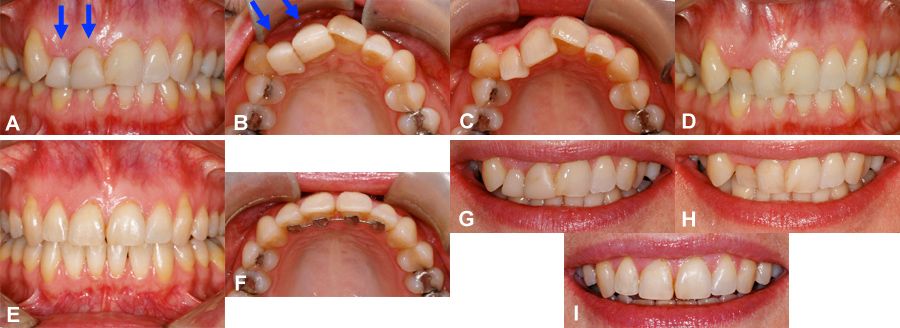

Camouflage esthétique – orthodontie instantanée

(A) La latérale et la centrale supérieure droite de cette femme étaient basculées vers l’intérieur (flèches) et ont été épaissies avec du composite. Une dent sévèrement penchée vers l’intérieur paraîtra toujours plus courte même épaissie. (B) Cette vue montre l’épaisseur du composite qui atteint 5-6 mm sur la latérale. Le point de contact entre les dents est difficile à nettoyer. (C) Avant de débuter l’orthodontie, tout le composite a été enlevé. La malposition sévère des dents est maintenant évidente. (D) Vue de face après l’enlèvement du composite. (E) À la fin de l’orthodontie, les surfaces avant des dents ont pu être alignées convenablement et la longueur des dents est plus proportionnelle et symétrique. (F) La surface interne des dents est aussi bien alignée. Une attelle de rétention augmente la stabilité des corrections. (G) Sourire avec les facettes épaisses. (H) Sourire après l’enlèvement des facettes de composite. (I) Sourire à la fin de l’orthodontie une fois les corrections terminées. Les dents ont des signes de décolorations et défauts d’émail qui pourront être corrigés par un dentiste restauratif si la patiente le désire.